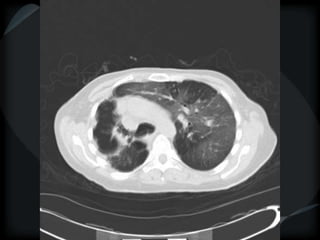

Reticular Pattern - NSIP

inflammation and fibrosis

 Predominantly basilar

 Significant ground glass

 Subpleural sparing low sensitivity, high specificity

 No honeycombing, some cystic change

 Traction Bronchiectasis

Diagnostic accuracy 50%

 Cellular NSIP

 Fibrotic NSIP

 Associated with CVD

 Undifferentiated CVD – T. King

NSIP- cellular

NSIP-fibrotic